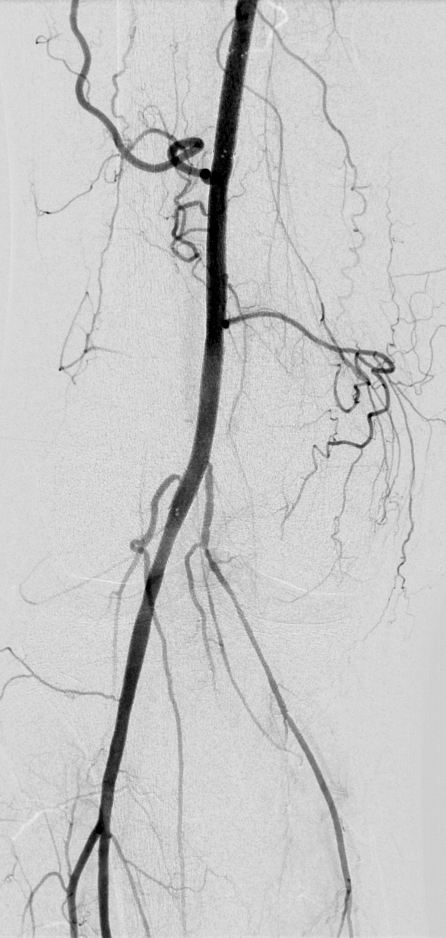

PERIPHERAL ARTERIAL DISEASE: CASE 1

74 year old patient with a history of non-insulin dependent diabetes, hypercholesterolemia, and hypertension who presents to our office with right lower extremity intermittent claudication. His history is also significant for coronary artery disease.